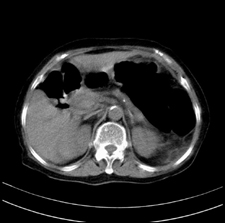

患者,女,75岁。腹痛,体黄5日,膝胸位时腹痛缓解。肝功能明日出来。彩超提示胆总管占位,未见血流信号。心电图提示s-t段改变。患者体质较弱,未能增强。

胆总管多发结石伴肝内外胆管轻度扩张。

胆总管上段,腔内有软组织密度影 ,ct值36-44hu。大家看有没有胆管癌的可能。

典型胆总管多发结石;增强扫描前后ct值是否发生改变是鉴别结石与占位的依据。